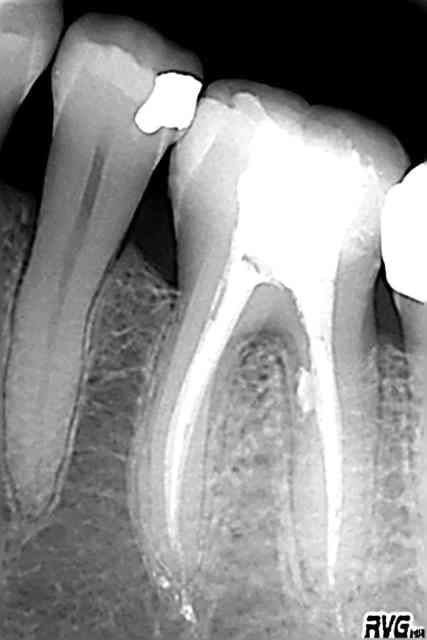

patient adressé pour réhabilitation haut gauche.

devis pour une greffe sinusienne + 4 implants.

le patient voulait absolument un bridge de sa canine à deux implants postérieurs, et sans greffe.

la preuve.

il voulait la meme chose qu'en bas donc...

S'il veut la même chose qu'en bas, impossible, il manque un apex oublié en secteur 2 (mais peut-être suis-je abusé par un artefact de ce remarquable cliché que tu n'auras pas pu ou voulu retoucher. ;)

Pourrais tu m'apprendre si la résorption osseuse autour des implants est due seulement à l'hygiène, la tabagie, ou l'option mixte retenue par le confrère?